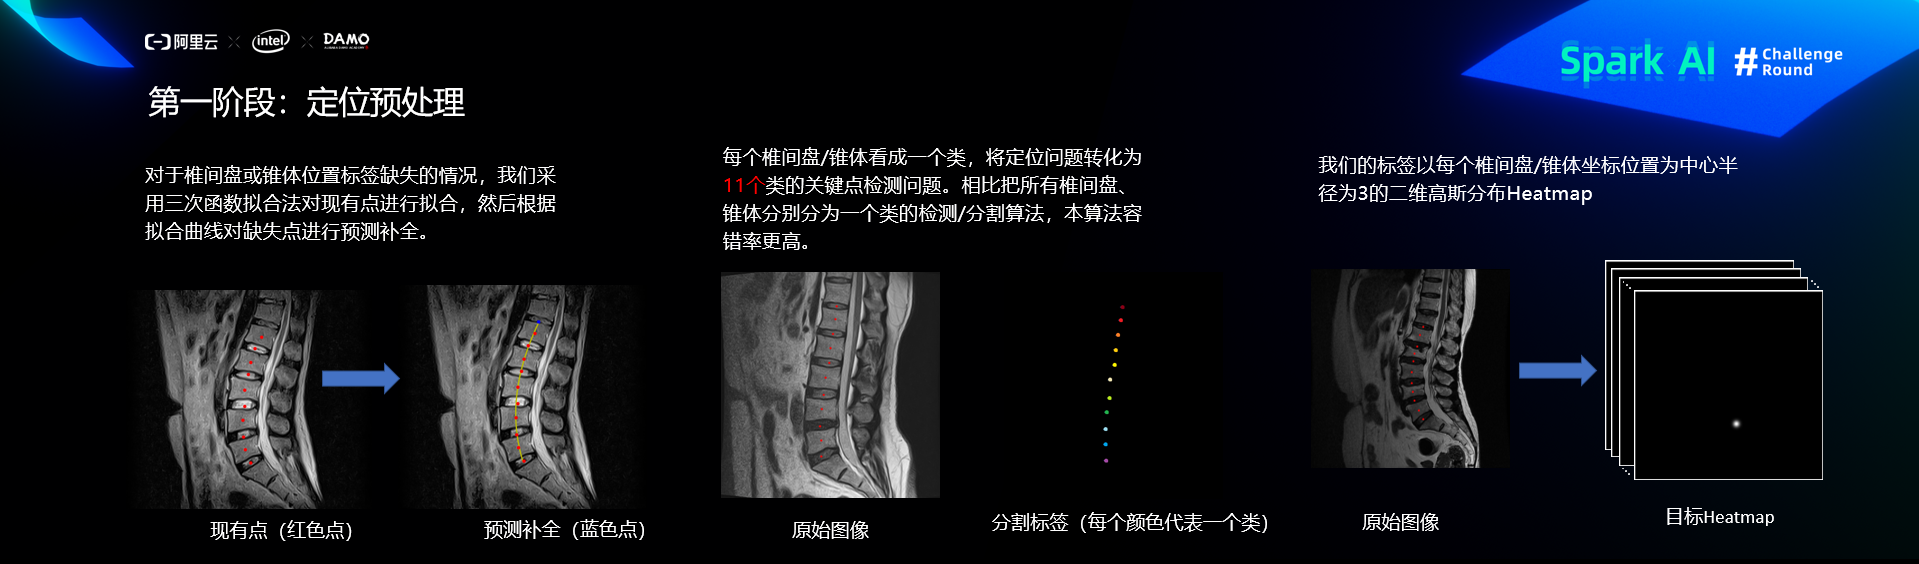

第一阶段:定位

预处理